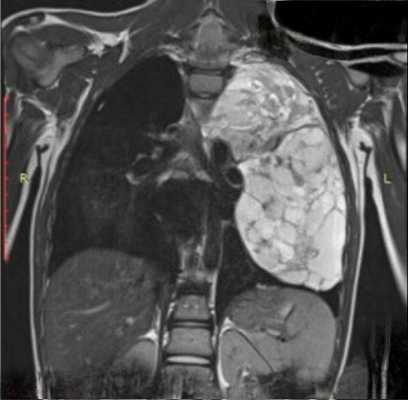

Диагностика лимфомы легких

Обычно медицинские специалисты отдают предпочтение МРТ, поскольку отсутствует лучевая нагрузка однако в случае с обследованием воздушной ткани легочной паренхимы, которая в норме практически не содержит жидкость, наиболее подробные результаты обследования и детализированное изображение можно получить с помощью КТ легких. Если лимфома выявлена на МРТ, и у врача есть подозрение, что раковые клетки мигрировали в костную ткань, то пациенту будет рекомендовано дополнительное обследование костей. В ходе компьютерной томографии исследуют ткани разной морфологии, попадающие в зону интереса: кости, внутренние органы, сосуды. Для диагностики последних необходимо дополнительное контрастирование.